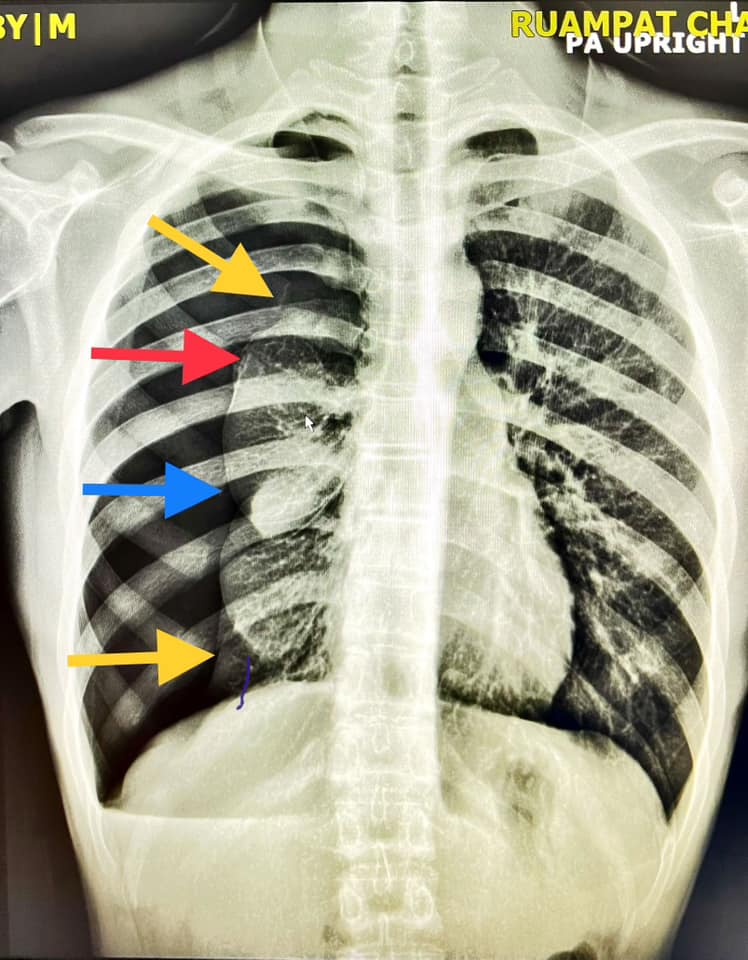

“เอ็กซเรย์ดังรูป วินิจฉัยเป็นอะไรดี #เจ็บหน้าอก เฉลยในคอมเม้นท์ #ENDS #VASP #EVALI #Ecigaretts #Vapes #Pods เพจแตกเพราะพวกคุณสนใจนะ เอาจริง ๆ ตอบไม่ทันทำไงดี ผมรบกวน* แชร์ไปเยอะ ๆ เลย เคารพทุกความคิดเห็นไม่มีอะไรผิดไม่มีอะไรถูกมันเป็นของใหม่

ต่อมาคุณหมอก็ เข้ามาโพสต์อธิบายรายละเอียดของเคสที่กล่าวไว้ข้างต้นต่อว่า “ใบ้ให้ด้วย arrow sign ครับ

สรุปเป็นลมรั่วในช่องปอดขวาทำให้ปอดขวาแฟบครับ ปลายลูกศรคือ ขอบปอดที่แฟบไปรวมกันเป็นก้อนตรงกลาง”

“โดยปอดขวามี 3 พู เลยยู่ไม่เท่ากันเห็นเป็นก้อนขรุขระ คนไข้จะมาด้วยเหนื่อยหรือเจ็บหน้าอกหายใจไม่สุด ซึ่งเคสนี้มาจากการใช้ Vape หรือพอด หรือ E cigarett บุหรี่ไฟฟ้านั่นเองครับ”